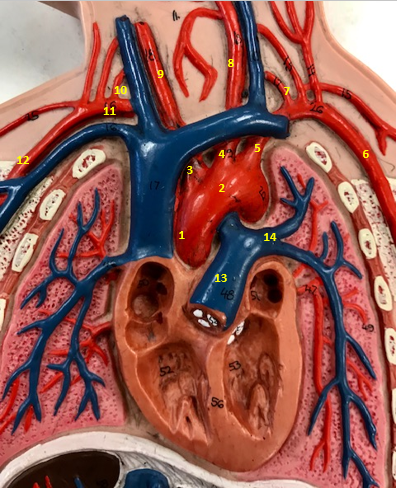

Aorta

Name #2

Brings blood out of left ventricle

Function of aorta

Brachiocephalic artery

Name #3

Supplies oxygenated blood to right arm shoulder neck and head

Function of brachiocephalic artery

Left common carotid artery

Name #4

Supplies oxygenated blood to left neck and head

Function of left common carotid artery

Left subclavian artery

Name #5

Supplies oxygenated blood to left arm shoulder

Function of left subclavian artery

Left axillery artery

Name #6

supplies blood to left armpit and upper limb

Function left axillary artery (6)

Left vertebral artery

Name #7

Supplies blood to brain and spinal cord

Function of left vertebral artery (7)

Left common carotid artery

Name #8

Supplies blood to left neck and head

Function of left common carotid artery (8)

Right common carotid artery

Name #9

Supplies oxygenated blood to right neck and head

Function of right common carotid artery (9)

Right vertebral artery

Name #10

Supplies blood to brain and spinal cord

Function of right vertebral artery (10)

Right subclavian artery

Name #11

Supplies blood to right arm and shoulder

Function of right subclavian artery

Right axillery artery

Name #12

Supplies blood to right armpit and upper limb

Function of right axillery artery (12)

Pulmonary trunk

Name #13

Bring blood out of right ventricle to lungs

Function of pulmonary trunk (13)

Left pulmonary artery

Name #14

Bring blood to left lung

Function of left pulmonary artery (14)